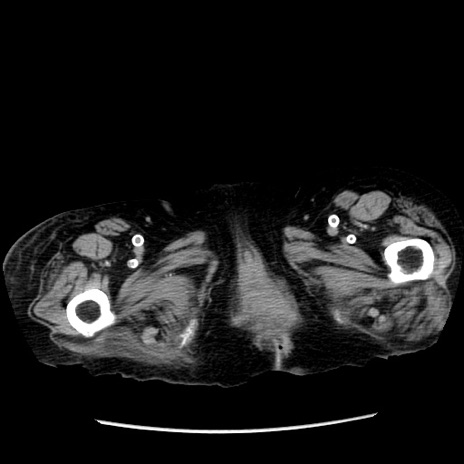

症例14(横断像)

【症例】 90歳代女性

【主訴】 腹痛・嘔吐

【現病歴】今朝から左側腹部痛を認めた。 経過観察していたが、嘔吐を認めたため来院。

【既往歴】 子宮癌術後

【身体所見】 意識清明、BP 127/54mmHg、P 98bpm Sp02 95%(RA)、BT 35.8°C、腹部平坦・軟腸ぜん動音聴取良好、右下腹部圧痛(+) 反跳痛なし

【データ】WBC 9800、CRP 0.46